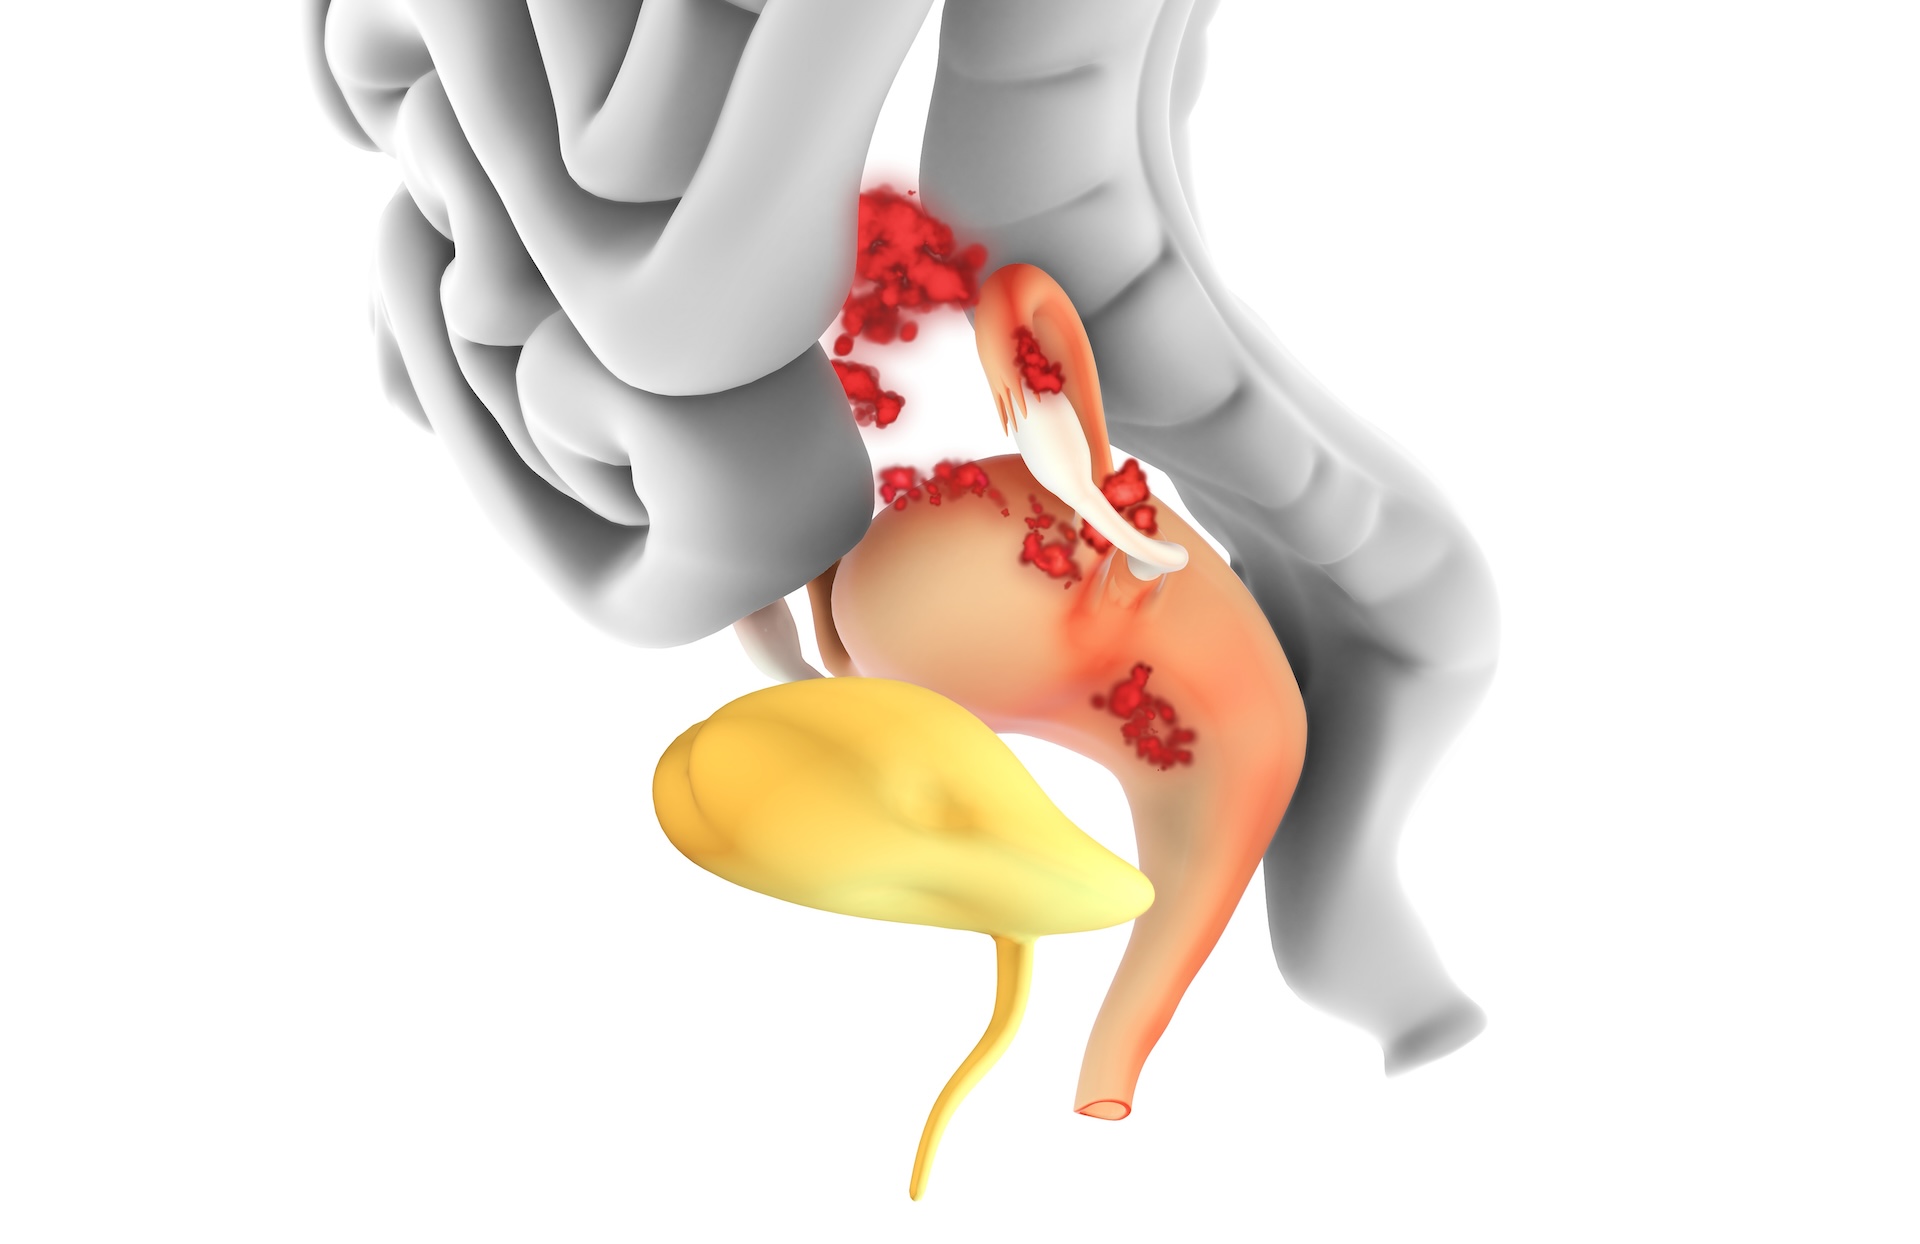

In people with endometriosis, immune cells appear to be less able to clear lesions. Yet, at the same time, people with endometriosis have higher levels of immune proteins such as IL-6 and IL-1β in their blood. These immune proteins, known as cytokines, are a type of messenger released by cells to promote inflammation.

Together, these dysfunctional cells make it possible for lesions to grow and persist. This immune dysregulation also has ripple effects across the body, contributing to the wide range of symptoms sufferers experience.

For instance, many people with endometriosis experience debilitating fatigue, cognitive difficulties (such as “brain fog”) and widespread pain. These symptoms are rarely emphasized in clinical guidelines, yet they’re often as disruptive as pelvic pain itself.